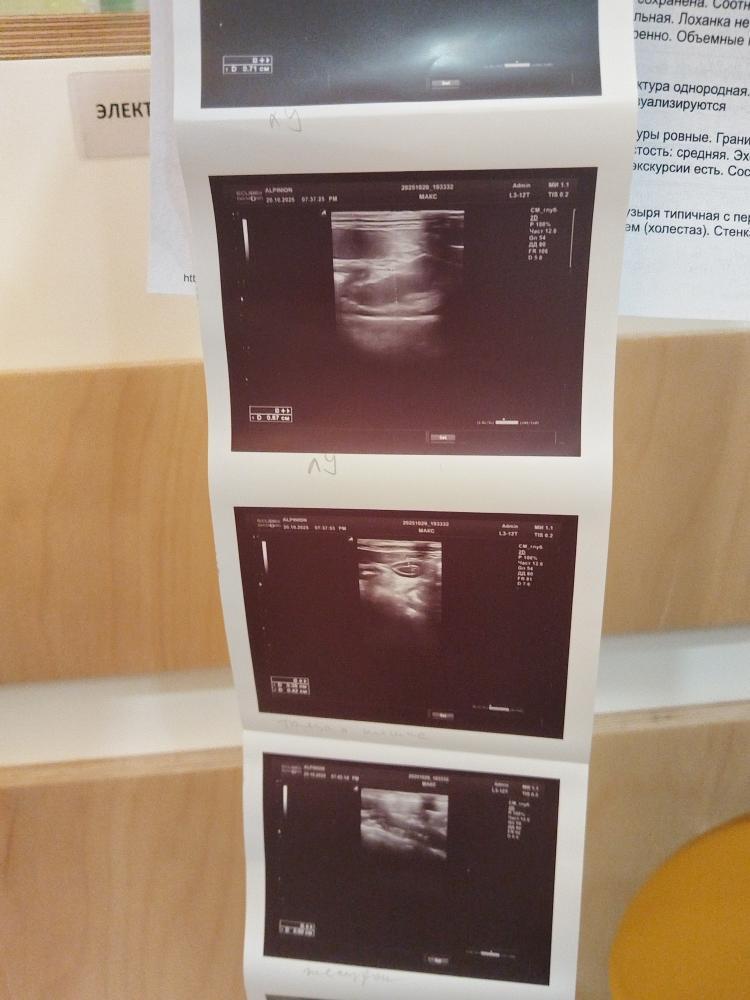

Ну, собственно, вот так.

Очень надеюсь, что мы прорвёмся.

Я сейчас ради примера выложу анализы, которые сделали в Волгограде. Оцените разницу.

Screenshot_20251021_191632_com.huawei.docs.jpg